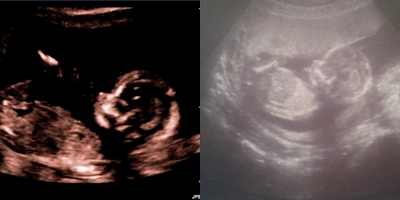

В 16 недель пошла платно на узи и сказали пол - СЫНОЧЕК ( я очень обрадовалась, в принципе пол мне был не важен, главное здоровье малыша). Дали фото и вот я решила сравнить первую Б и вторую (срок почти одинаковый). Сомнения пока в поле второго малыша есть (жду второй скрининг, ведь очень часто ошибаются с полом на таком раннем сроке).

А вы сможете определить кто где и существует ли такая "странная" теория на счет головы малыша и пола